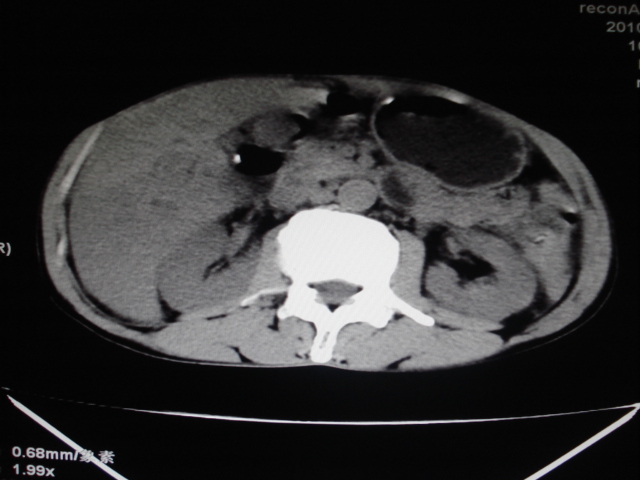

标题: CT24041:肝脏占位,请会诊!

男性,62岁。肝右叶占位,平扫及增强如下,延迟期为15分钟扫描。